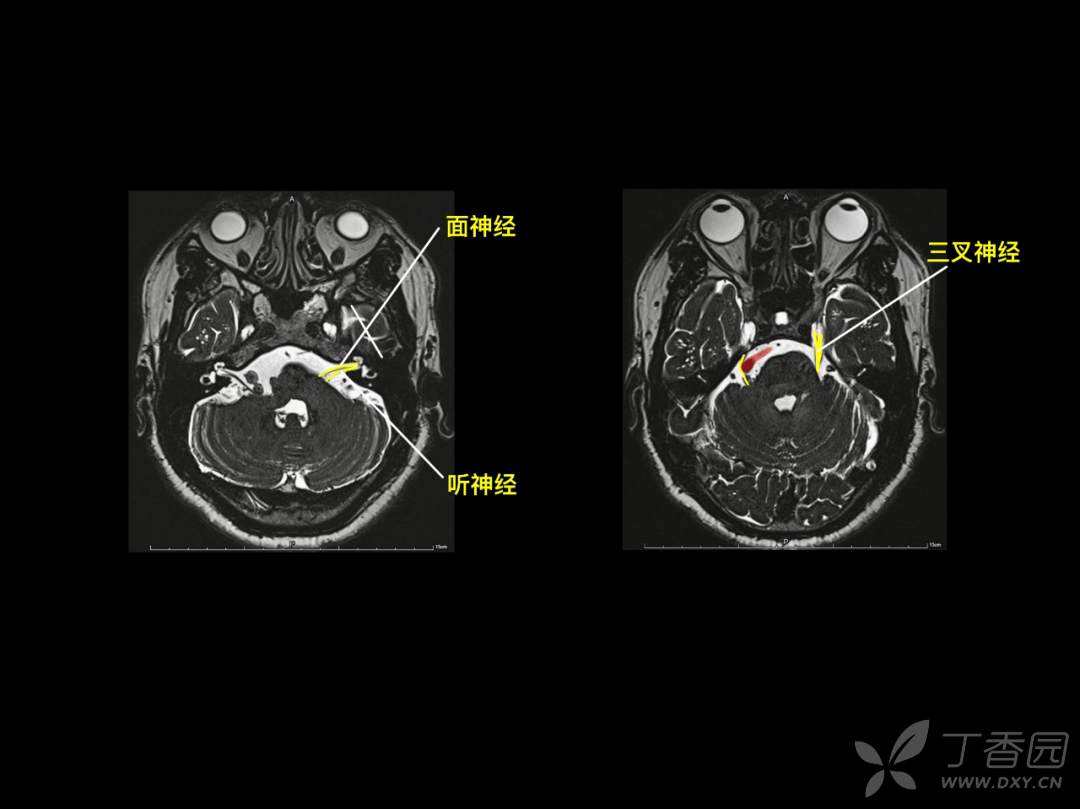

神经专业,要求「定位和定性」,先定位,后定性。与 CT 相比,颅脑 MR 可以更多、更清晰的呈现脑组织的解剖结构,神经专业的医生如何在颅脑 MR 的断层成像上去定位?

要么,你有「超级大脑」可以一层层的去记忆,「太难了」!那你也许会喜欢基于 「keypoint」的阅片方法,比如「苹果」外形、「Ω 征」、「M 征」等。本篇精华版 essay 希望给大家带来不一样的 MR 阅片技巧。

神经内科存在很多“征”,有助于帮助大家记忆!